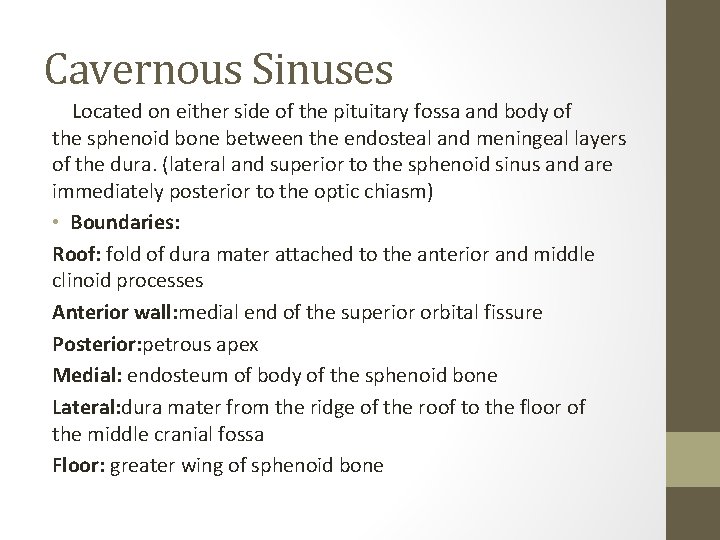

Cavernous Sinuses Located on either side of the pituitary fossa and body of the sphenoid bone between the endosteal and meningeal layers of the dura. (lateral and superior to the sphenoid sinus and are immediately posterior to the optic chiasm) • Boundaries: Roof: fold of dura mater attached to the anterior and middle clinoid processes Anterior wall: medial end of the superior orbital fissure Posterior: petrous apex Medial: endosteum of body of the sphenoid bone Lateral: dura mater from the ridge of the roof to the floor of the middle cranial fossa Floor: greater wing of sphenoid bone